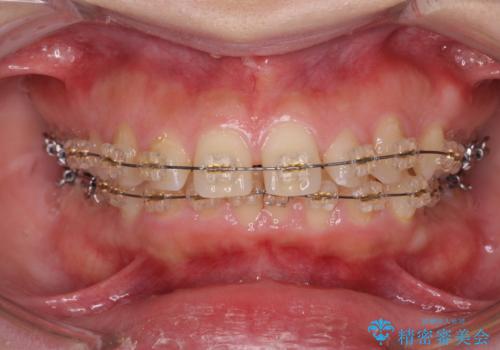

深い噛み合わせ、すきっ歯の改善 ワイヤーを用いたマルチブラケット矯正

- 噛み合わせが深く、前歯が突き出て隙間が出てきたことの改善を希望され矯正治療の相談で当院に初診来院されました。

ワイヤーを用いたマルチブラケット矯正を行うことで深い噛み合わせを改善し、前歯の隙間もなくし審美的な歯列へと治療をおこなっていきます。

深い噛み合わせの改善は前歯の圧下が必要なため、治療期間が長期化することが多いです。